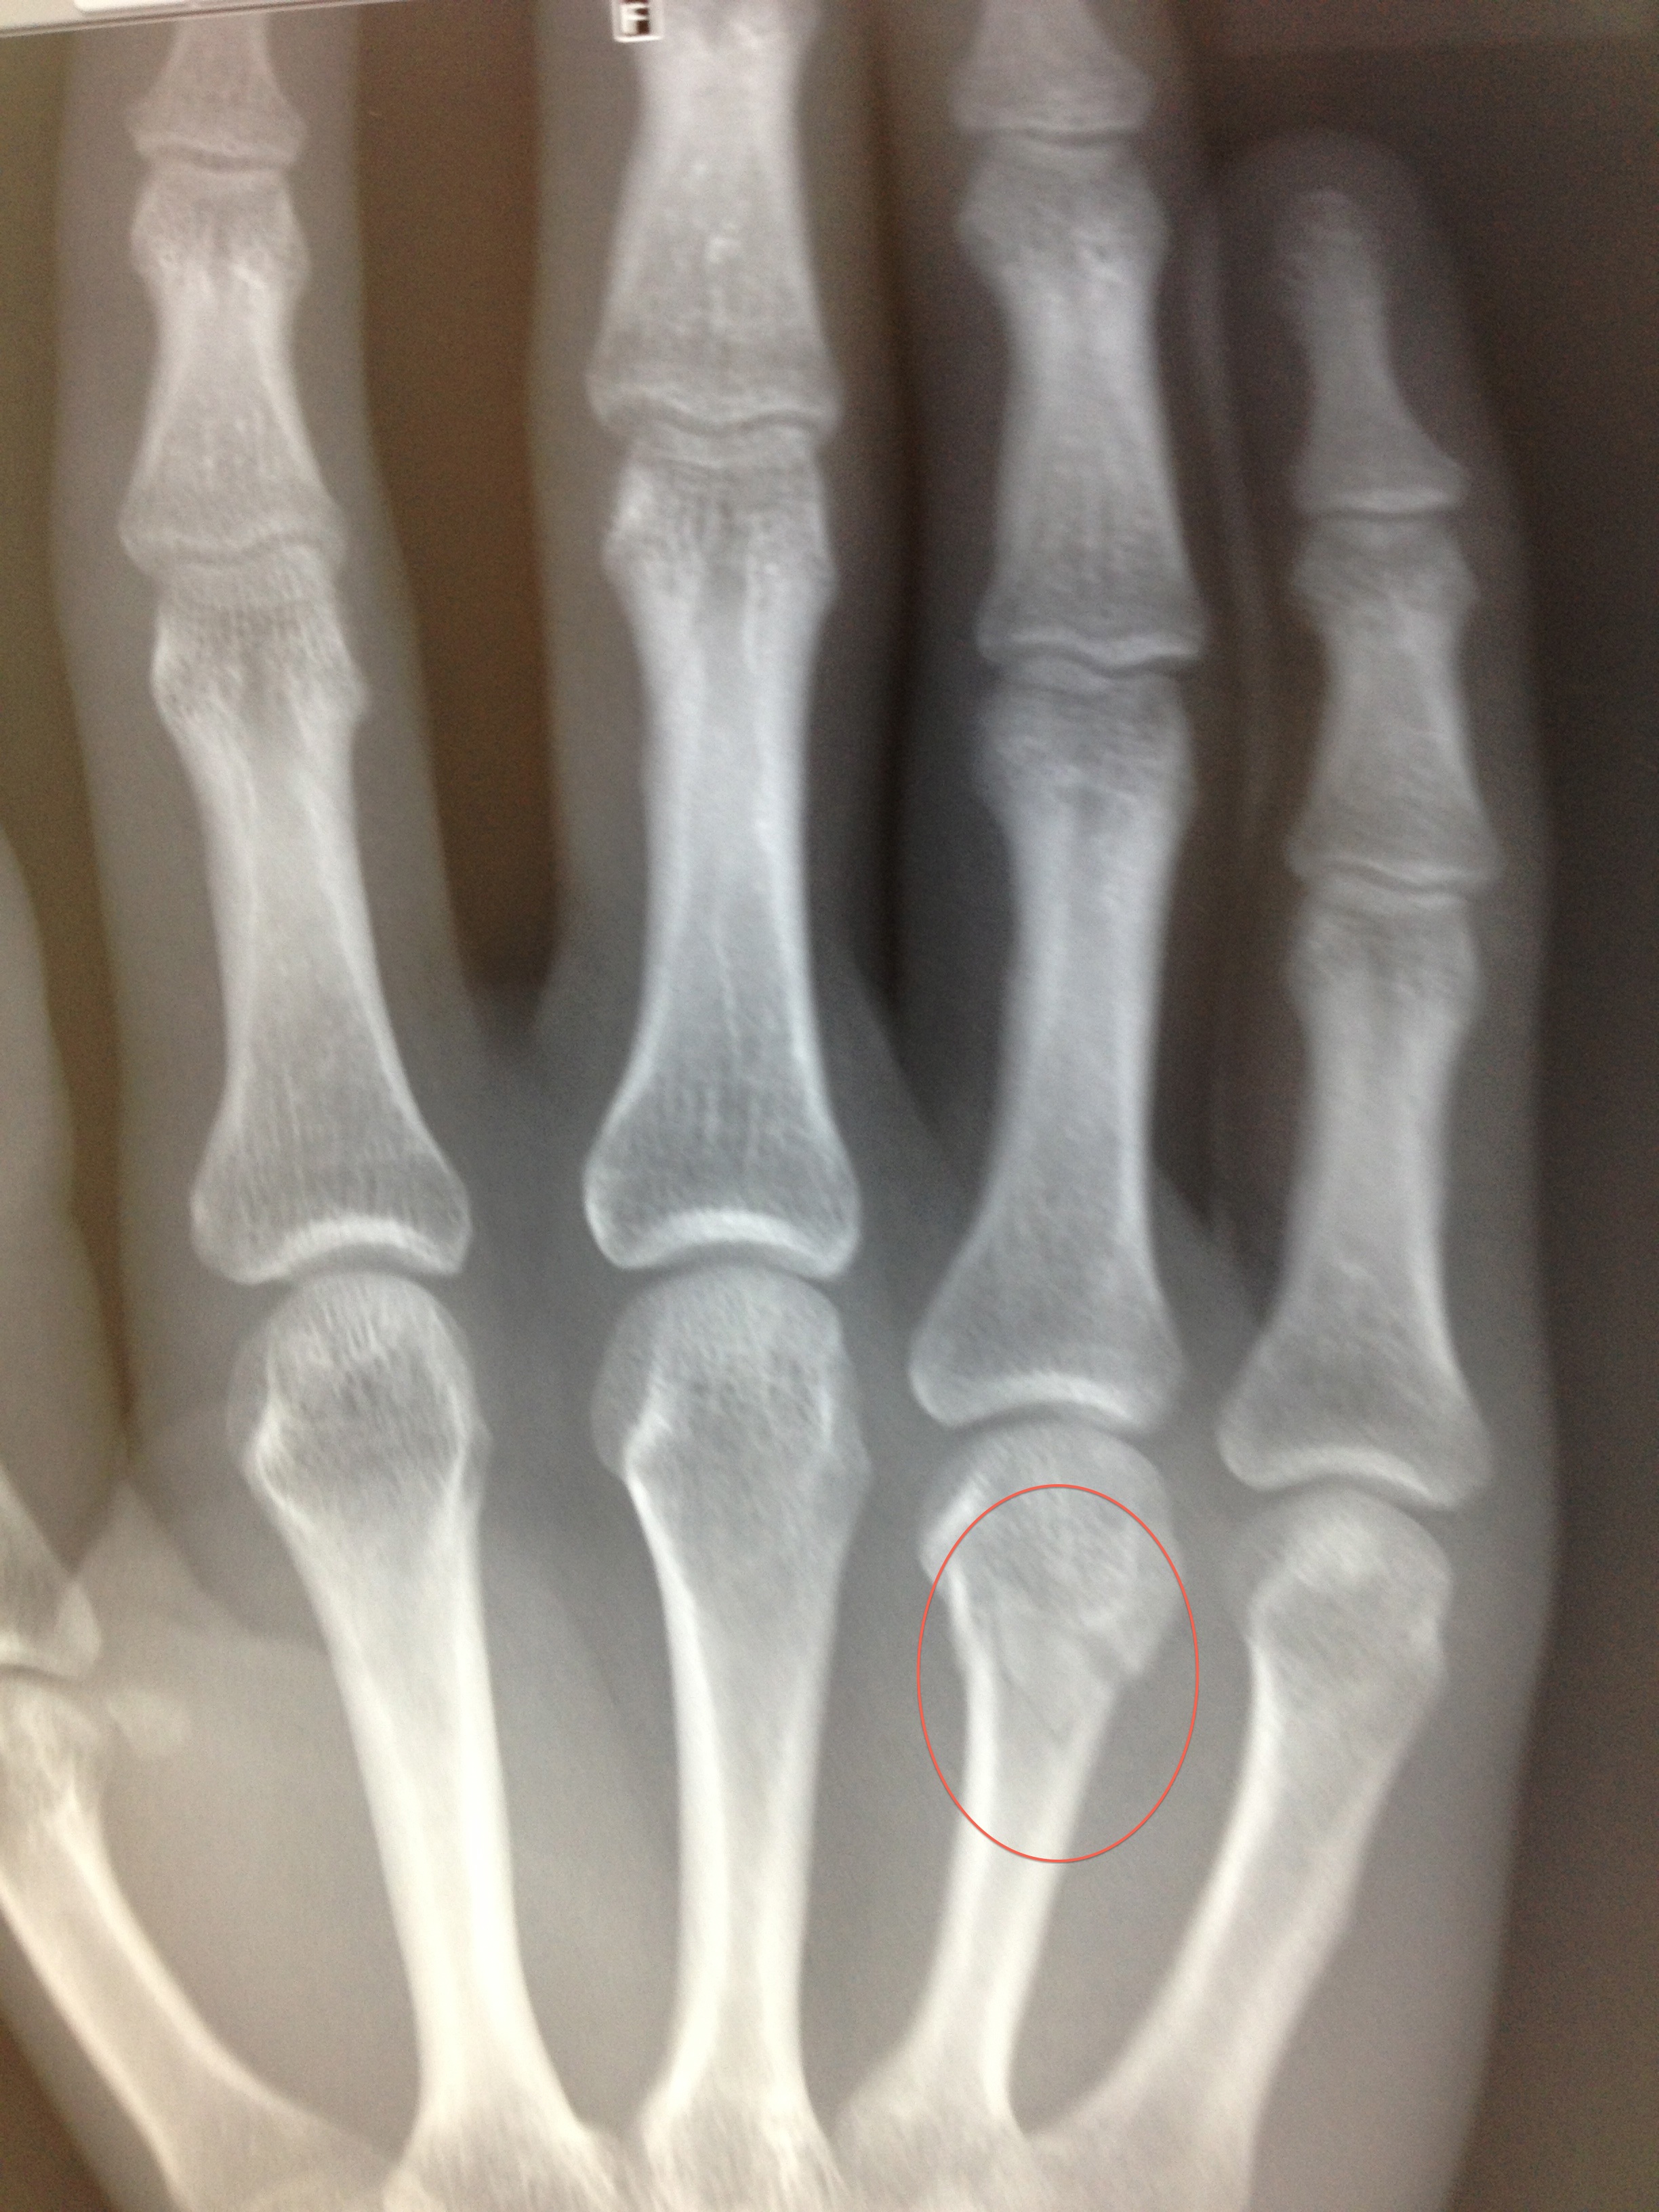

Walking down the stairs in my house, I slipped on a step and landed on my fist, breaking the 4th metacarpal (bone in the hand). As I landed I felt and heard a crack. A quick inspection of the hand revealed the knuckle of my ring finger on my right hand had disappeared – it was totally flat!

An X-ray at the hospital confirmed a cracked bone, but luckily there was no displacement which means the bone should heal just fine with minimal help. The care for the injury involves buddy strapping the ring and little finger on my right hand and trying not to aggravate the injury for the first 72 hours. On top of that I have to ice the injury and keep the hand as immobile as possible to prevent it moving and causing pain!

The doctor who examined the x-rays said that it will take at least 6-8 weeks for the bone to heal, but I will probably experience pain in the injury for a good few weeks afterwards. Hopefully on the pain front, he is wrong! In the meantime, I have to keep the ring and little fingers buddy strapped to prevent aggravation of the injury.